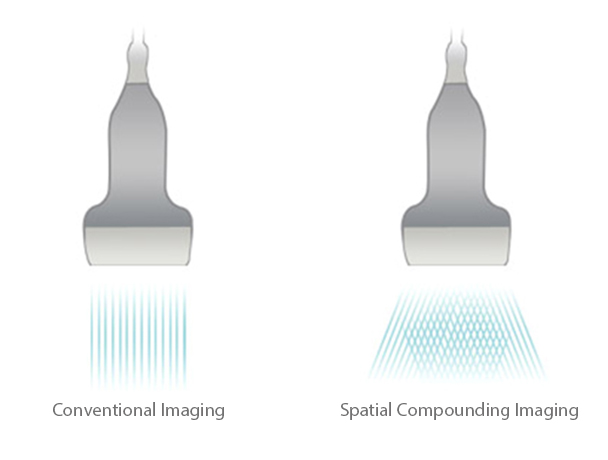

iBeam™

Permits multiple scanned angles to form a single image, resulting in enhanced contrast resolution and improved visualization.